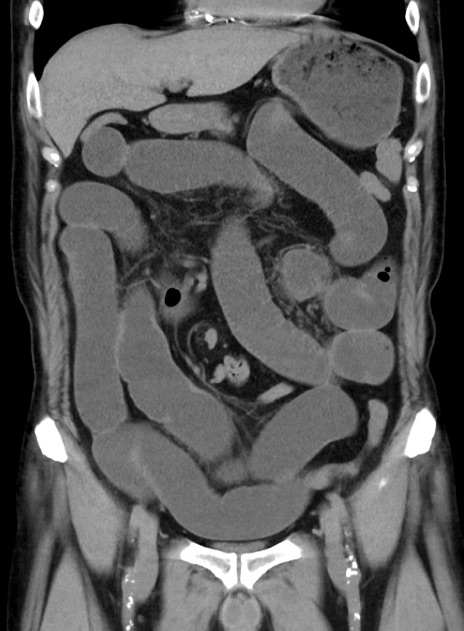

症例38(冠状断像)

【症例】70歳代 男性

【主訴】腹痛・嘔吐

【現病歴】昨晩より、嘔吐・腹痛あり。今朝になっても嘔吐あり。来院。

【既往歴】心臓バイパス手術、開腹胆摘、腸閉塞

【身体所見】BP 107/71mmHg、HR 116/min、腹部:平坦、軟、下腹部に軽度圧痛あり。反跳痛なし。

【データ】WBC 15100、CRP 0.32